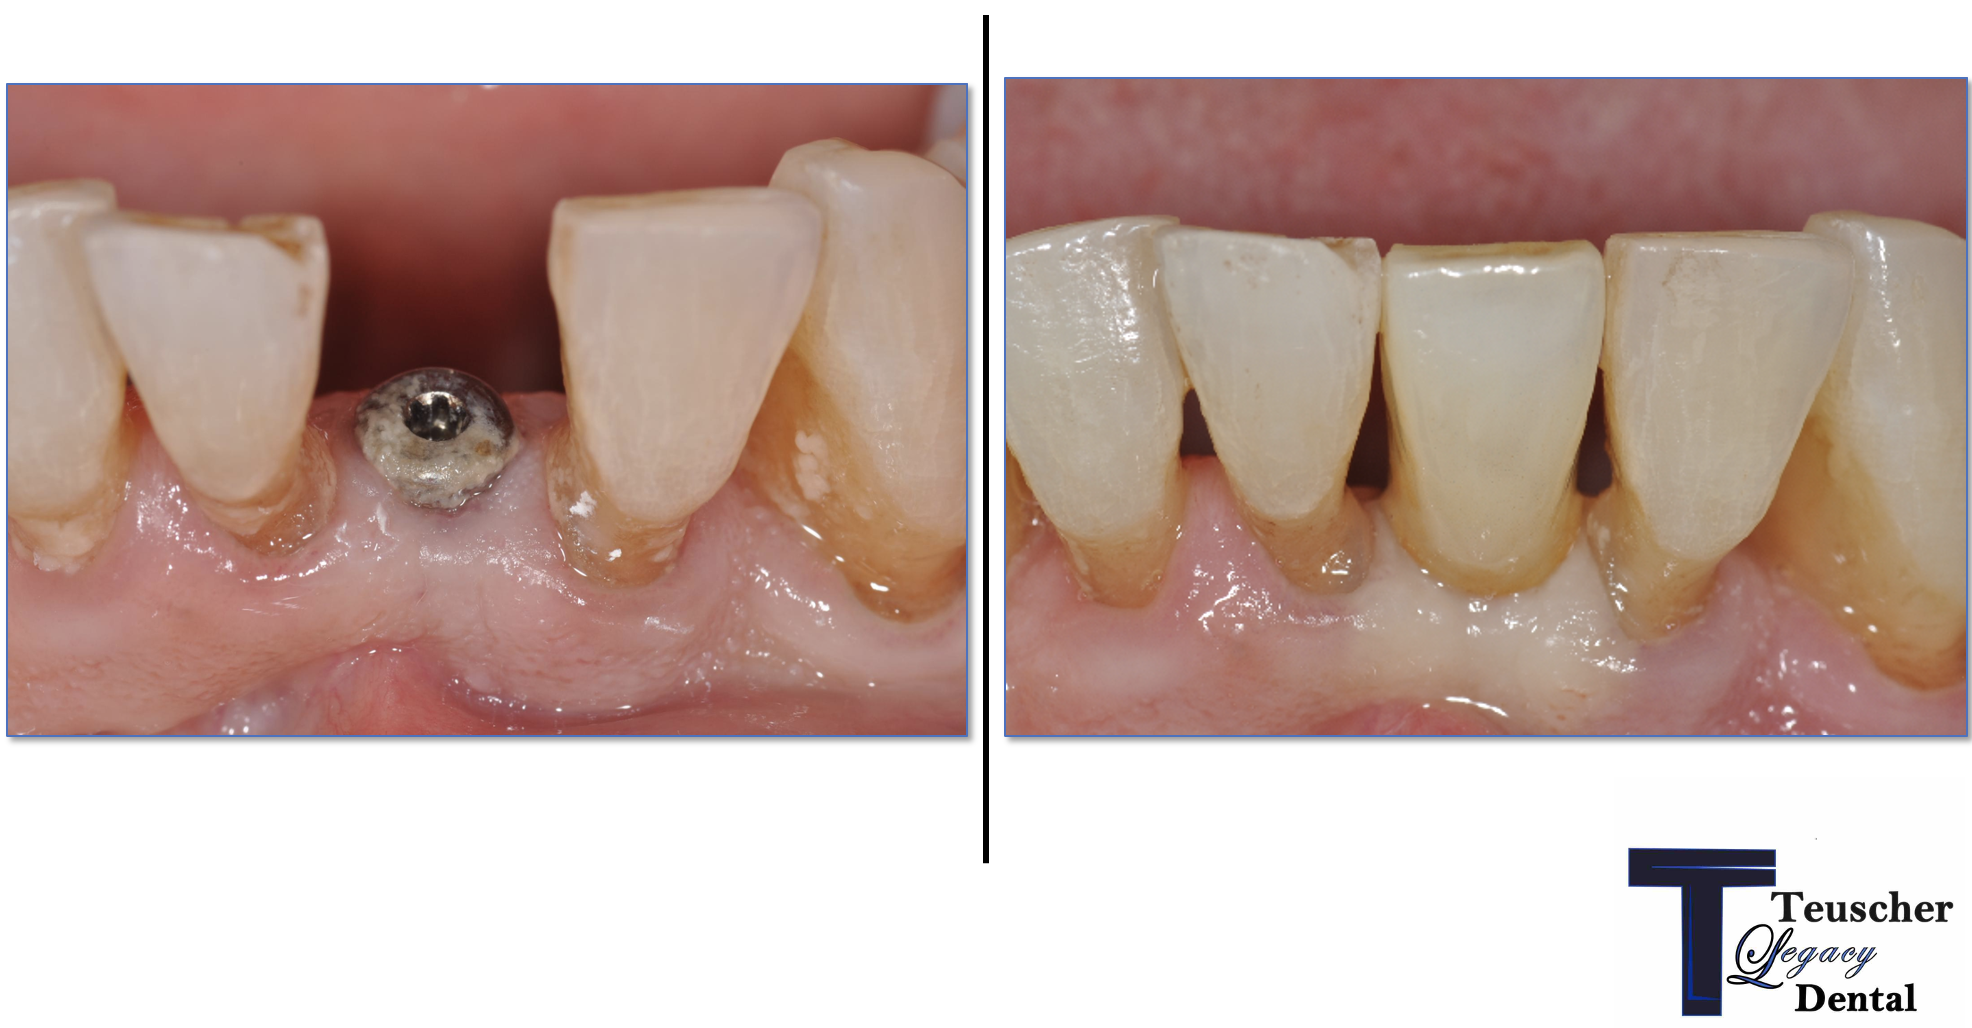

A: Yes! Here is a detailed video and break down of an immediate implant in a cosmetic case we did recently for a patient from St Charles, IL.

The before and afters we show are not stock photos like you’ll see on other websites. These are our real patients smiles, all neighbors in the Campton Hills area. This is why families across Kane County trust Teuscher Legacy Dental. In fact, we won an award for The Best Cosmetic Dentist in St Charles, Illinois. Check our Google Reviews!